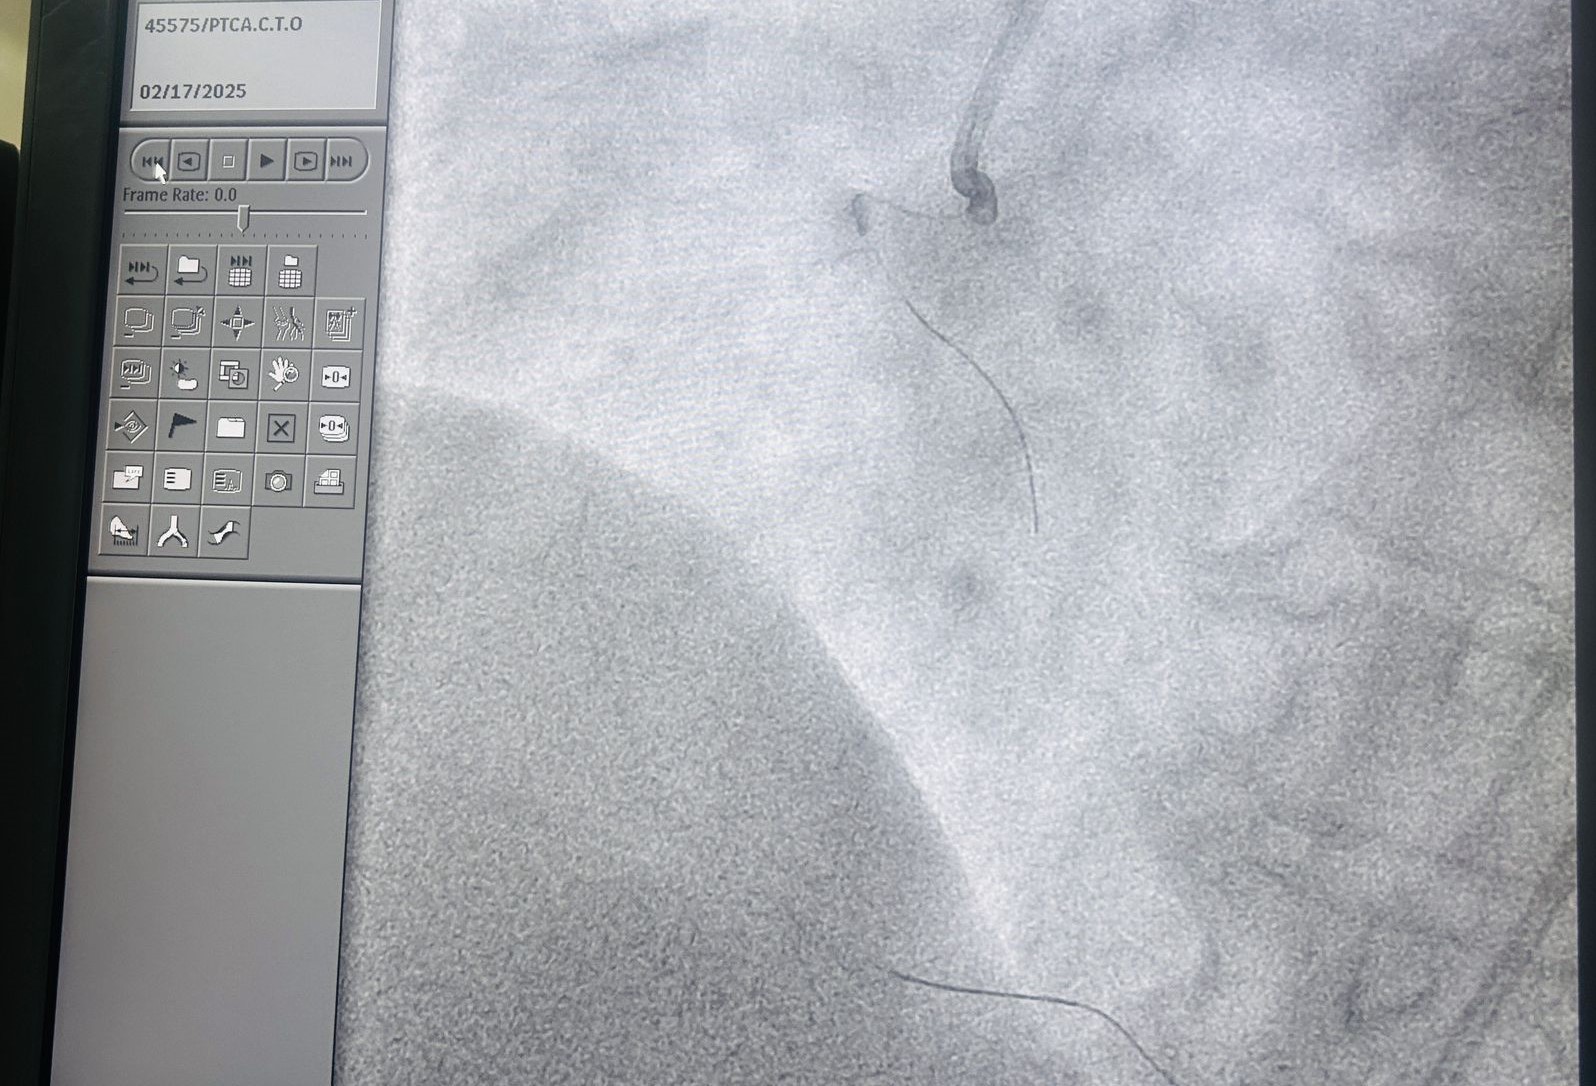

CTO workshop at Max Shalimarbagh New Delhi 17 Feb by Dr.Naveen Bhamri, good discussions on live cases

• Case image